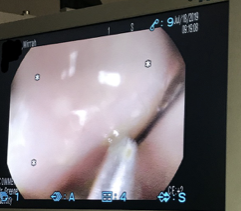

Mirrah was sedated and placed under anesthesia. The endoscope was passed through her mouth and esophagus into her stomach. Endoscopic forceps were used to grip the needle, and the needle and thread were removed. Mirrah was taken off of anesthesia after her procedure and woke up soon after. She relaxed in her kennel at IVS and was supervised until she fully recovered from anesthesia.